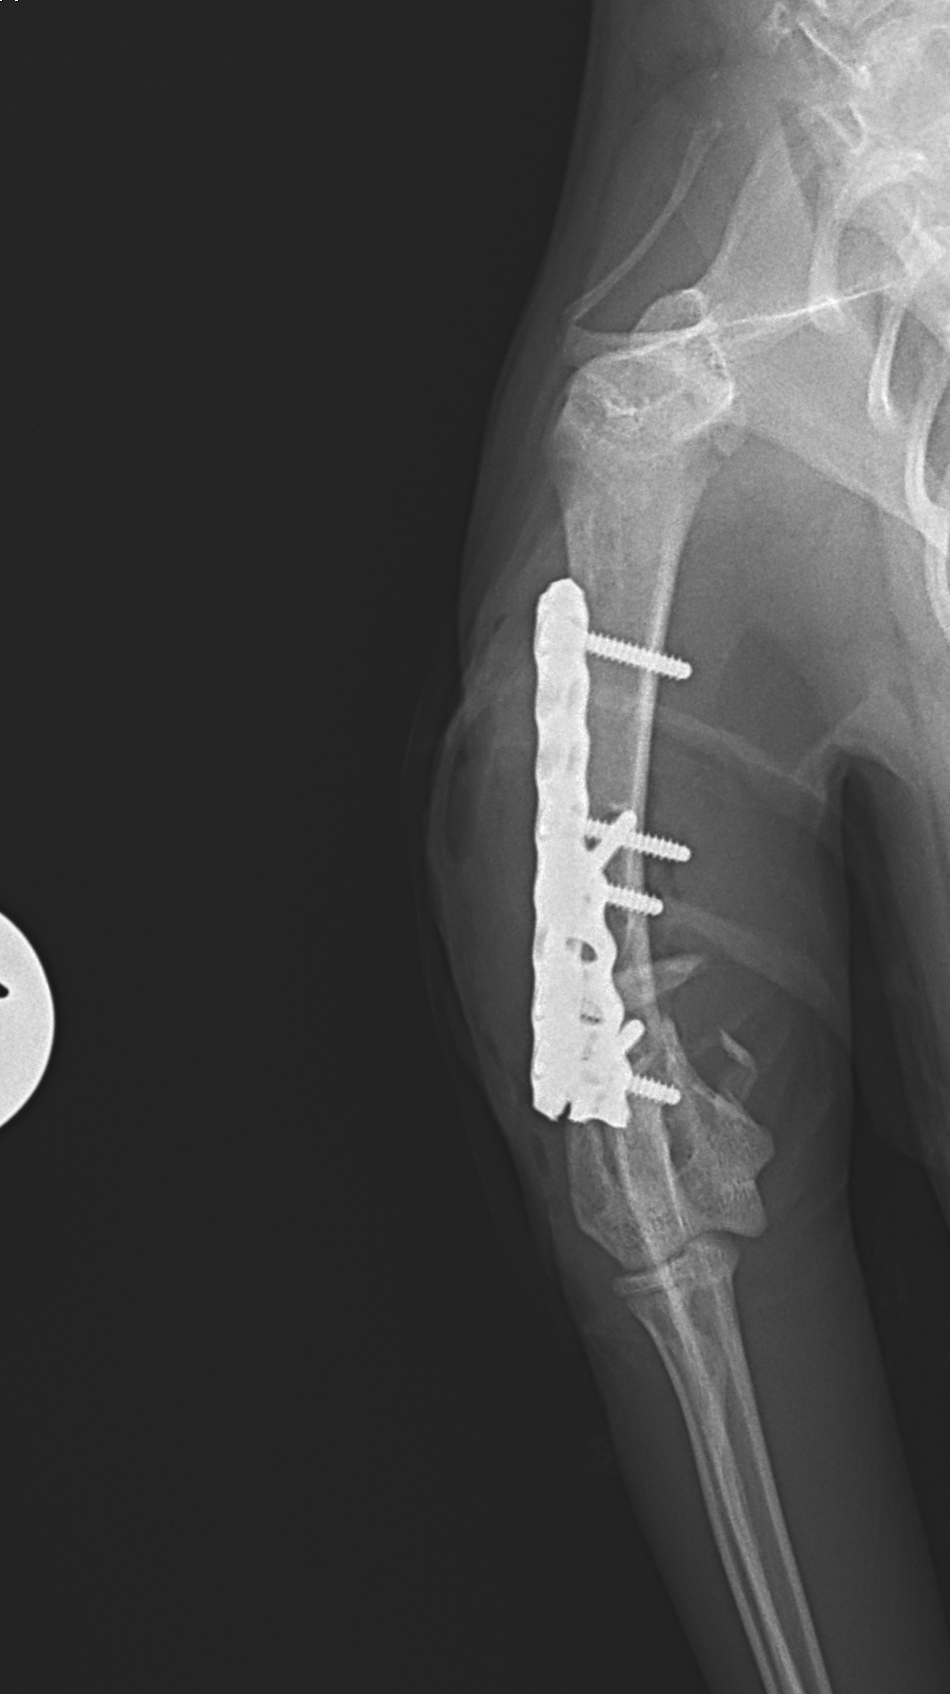

上腕骨遠位粉砕骨折

若い猫ちゃんが部屋で遊んでいたところ、不運にも上腕骨を粉砕骨折してしまったとのこと。かかりつけ医から固定術の依頼がありました。粉砕部分をOrthogonal Plateで固定術を行いました。